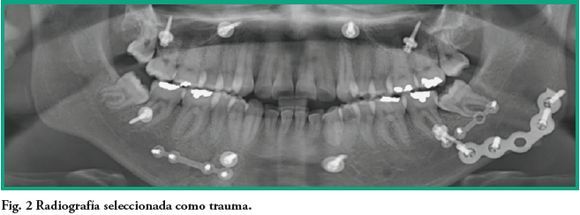

El análisis por diagnóstico presuntivo, mostró mayor frecuencia de imágenes compatibles con anomalía dentofacial 105 (60,7 %) que compatibles con trauma 53 (30,6 %) (p=0,00000002). Con respecto a las imágenes asociadas a impresión diagnóstica de trauma (fig 2), 32 (60,4 %) corresponden al género masculino y 21 (39,6 %) al femenino (p=0,0003). Se calculó una relación de riesgo (Odds Ratio) de 3,42 para los hombres. El grupo de edad entre 21 y 30 años presentó mayor cantidad de trauma con 21 radiografías (39,6 %) y el de menor cantidad fue entre los de 51 y 60 años con 3 pacientes (5,6 %). La distribución anatómica del trauma se resume en la tabla 2.